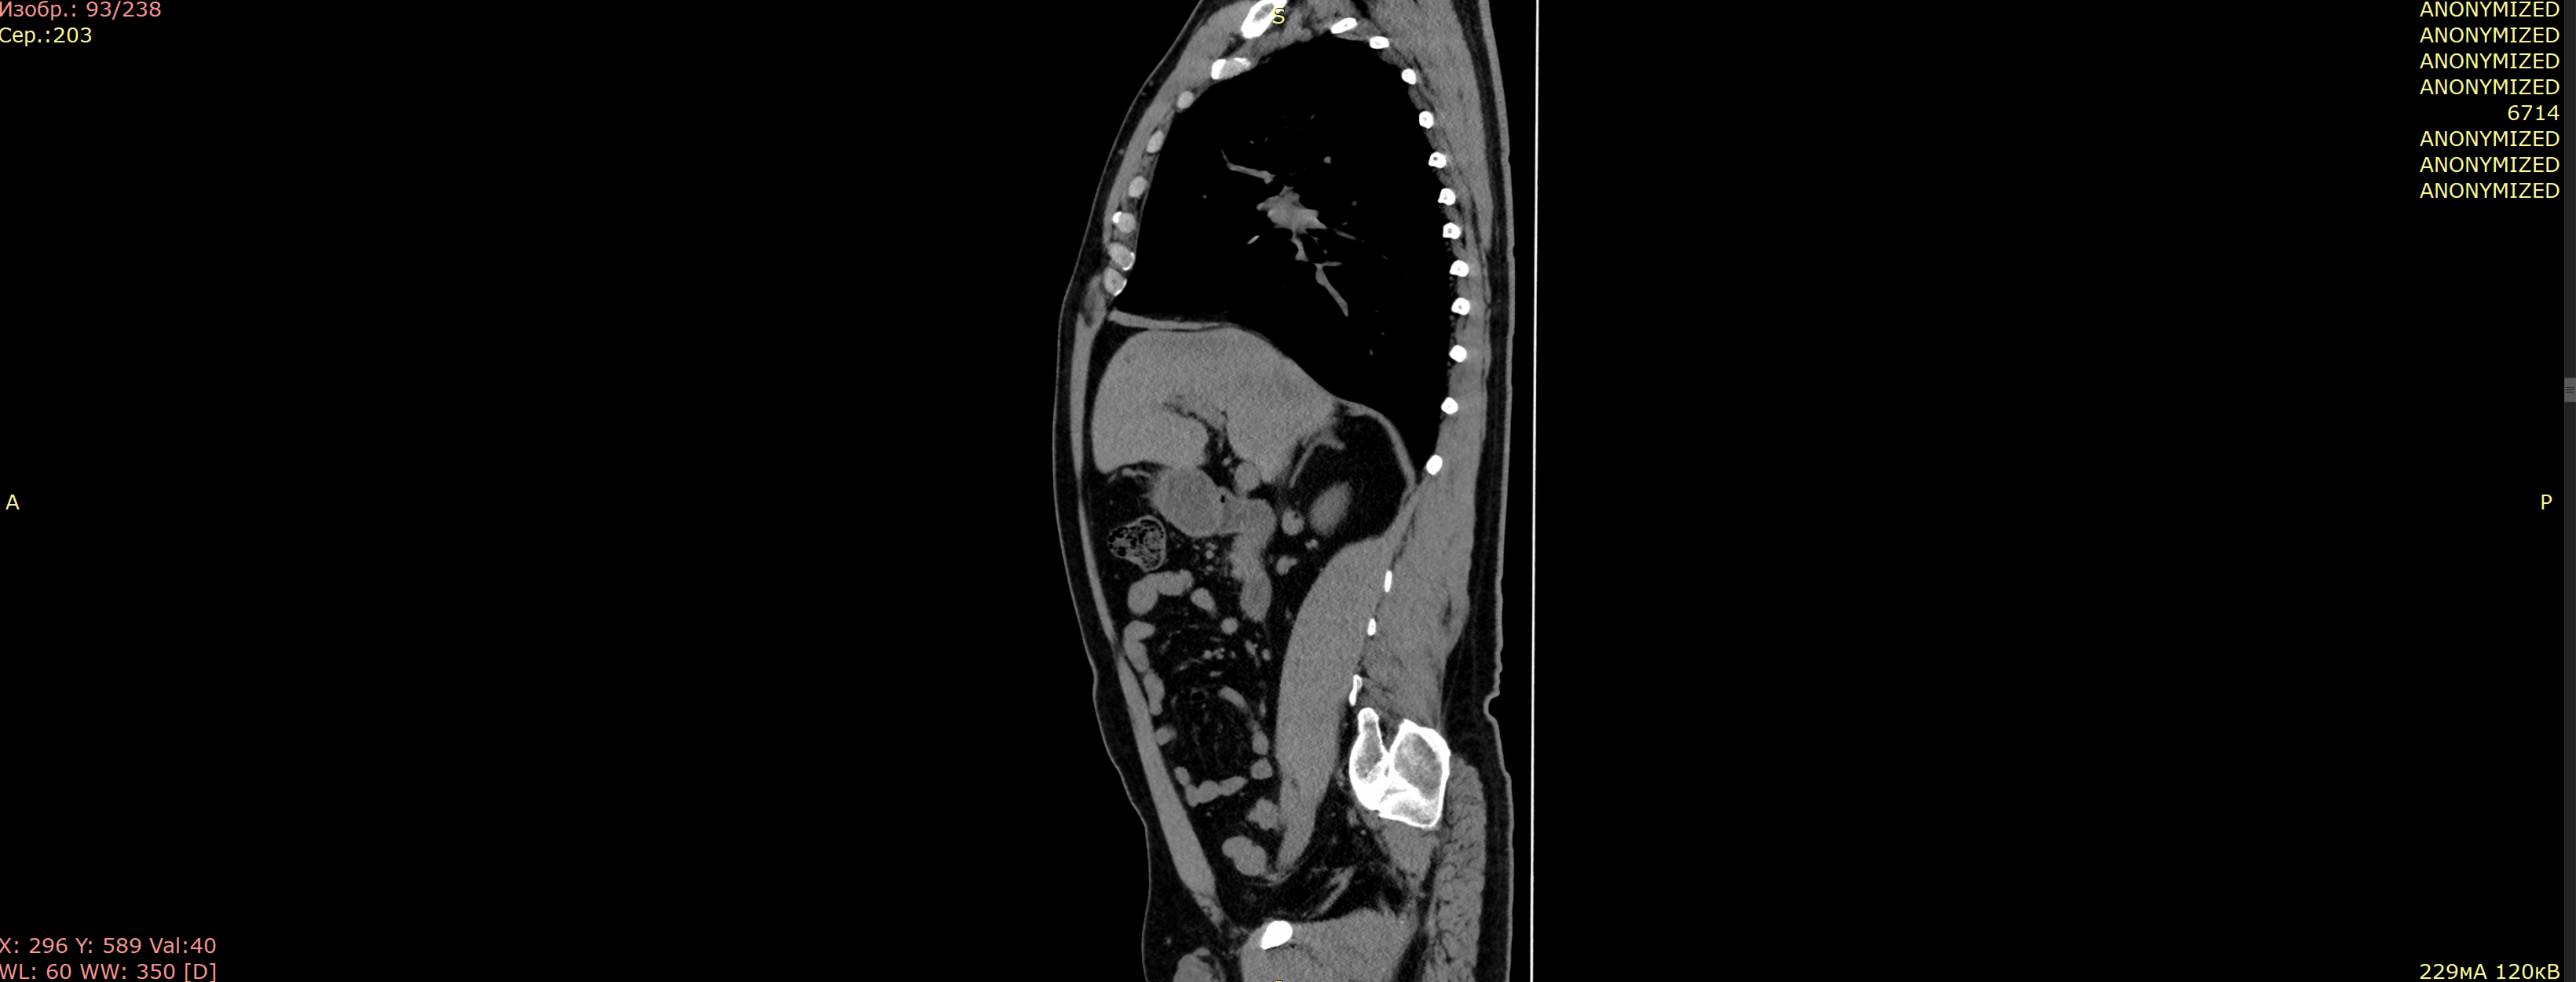

Результат анонимизации DICOM

🖼️ Пример анонимизированного файла

Пример анонимизации DICOM

Все персональные данные заменены на "ANONYMIZED"